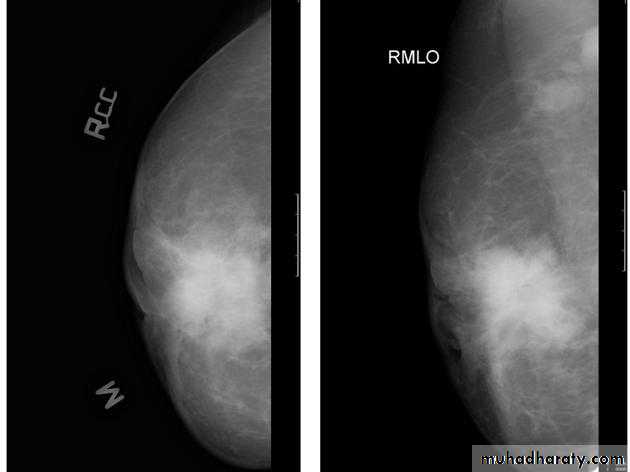

The craniocaudal view (CC view), is one of the two standard projections in a screening mammography. It must show the medial part as well the external lateral portion of the breast as much as possible.

The mediolateral oblique (MLO) view is one of standard mammographic views. It is the most important projection as it allows to depict most breast tissue.